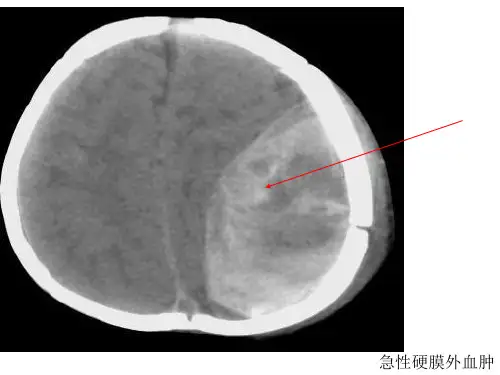

头颅CT显示:广泛脑挫裂伤,左侧额颞顶部硬膜下血肿,量约[X]ml,脑中线结构明显向右移位,脑室受压变形。